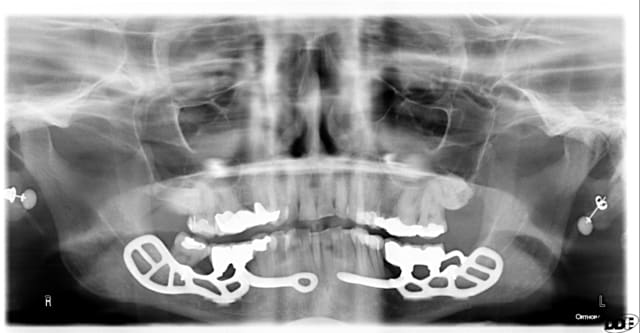

Les plaques existent depuis environ une dizaine d années

Je suis un des tous premiers à en avoir posé en dehors de GS puisqu à l époque il m en a confié une pour poser à la mandibule chez une patiente où je n avais pas pu poser un monodisk

J ai posé cette plaque en quais totalement enfoui à l époque : elle tjs là totalement indolore, bien sonore comme un cylindre

Je vais te filer qques photos d une patiente opérée voici 3 ans avec du nano et des plaques rien que l aspect de la muqueuse te montrera que tout ça est sain et ossifié

Merci, je me souviens bien de ce cas déjà présenté.

Le volume est en effet bien plus grand après, mais je me permet d'avoir quelques doutes sur l'intégration des plaques au niveau osseux...reste à avoir des études et des statistiques sur quelques centaines de cas, voir plus ;-)

Ben des études statistiques moi j en ai pas... J ai que mes propres cas

Par contre je peux te dire que les 4 plaques et même le monodisk sont sonores et parfaitement indolores donc a priori intégrés béton